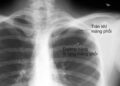

Các biến chứng của bệnh đậu mùa khỉ có thể bao gồm các nhiễm trùng thứ phát, nhiễm trùng huyết, viêm phế quản phổi, viêm não và nhiễm trùng giác mạc có kèm theo mất thị lực.